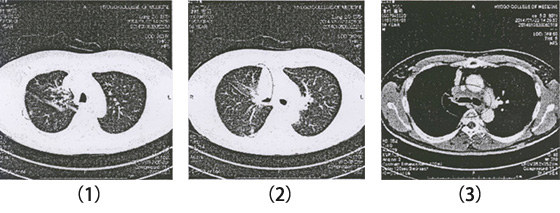

漢方治療前

漢方治療前、抗がん剤で腫瘍がやや縮小。その後、全身状態が悪く抗がん剤中止。

漢方治療1年後、原発巣が消失されて、肝転移も消失された。

漢方治療1年後、肺転移がほぼ消失された。